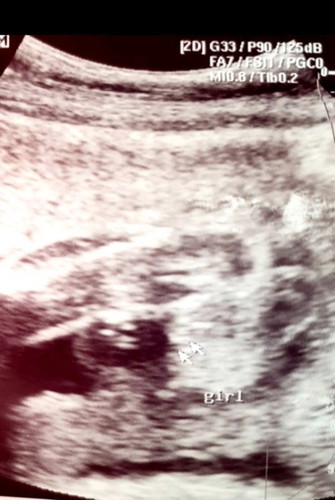

60% Girl si baby

Hi po. Sabi po ni Ob 60% girl daw c baby. Ano po sa tingin nyo pwede pa kaya magbago? May mga momsh po ba na sabi girl tpos nging boy? 24 weeks preggy po. First time mom and excited po. Kaya Iniisip ko ndn po kc bumili ng mga gamit ni baby habang maliit pa tyan ko. Thank you po sa sasagot!

Parang girl naman sa ultrasound momshie. Pero kung si OB mismo nagsabi na hindi 100% sure, retry na lang after few weeks. Kung bibili ka ng gamit ni baby, pang newborn na lang muna. White lang naman yun kaya ok lang. :)